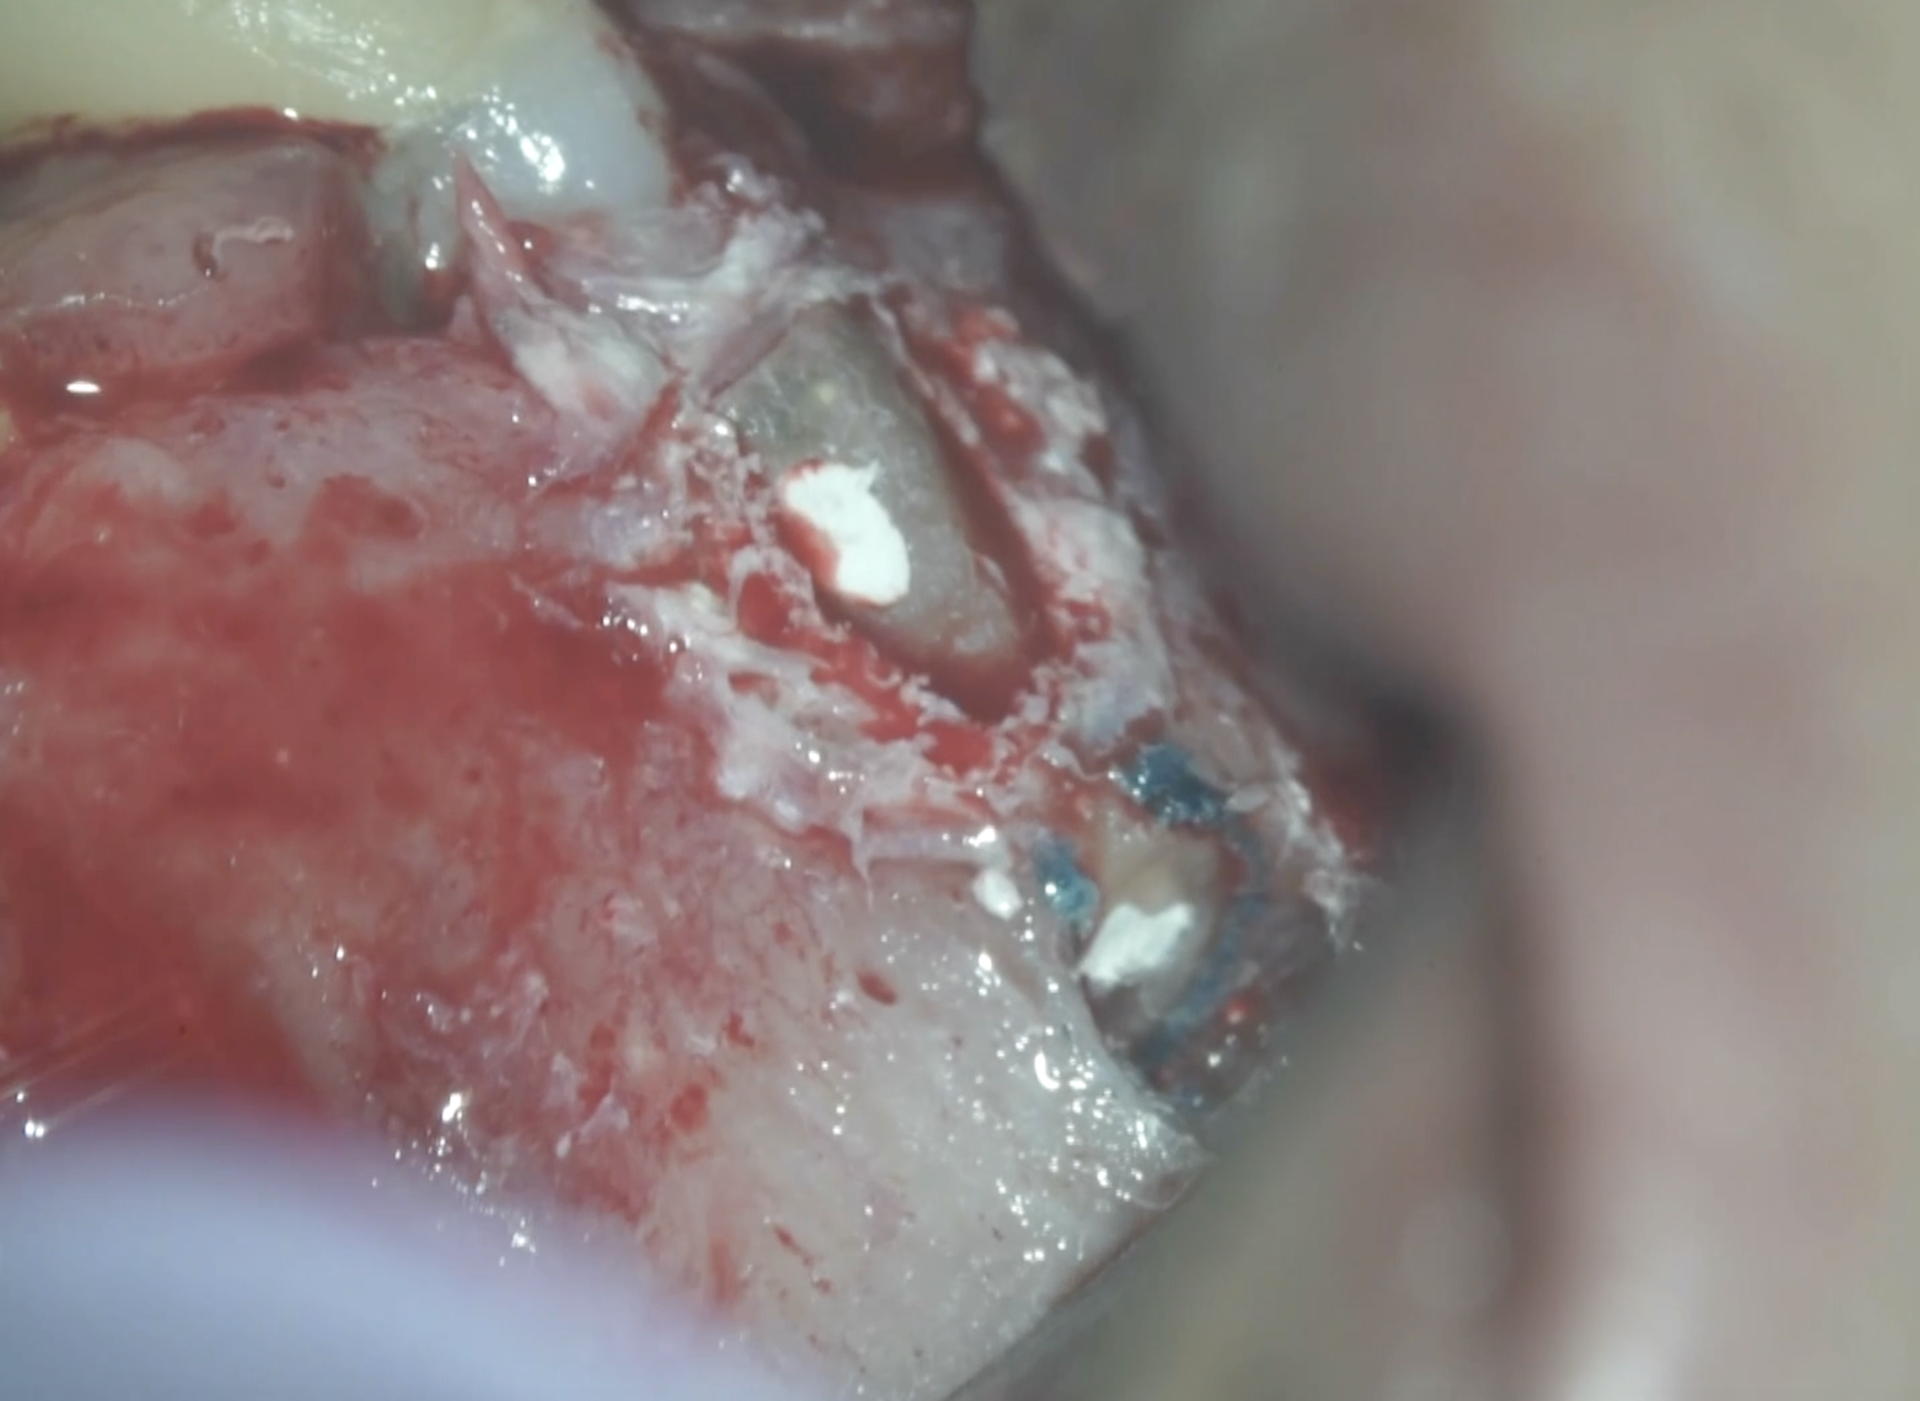

まず穿孔部を明示する。

外部吸収を封鎖したBC Linerは脱離していない。

その後、Apicoectomyへ移行する。

根を切断後にメチレンブルーで染色し根管を確認した。

この後にRetroprepを行う。

この後に穿孔部も形成した。

この後に両方を充填する。